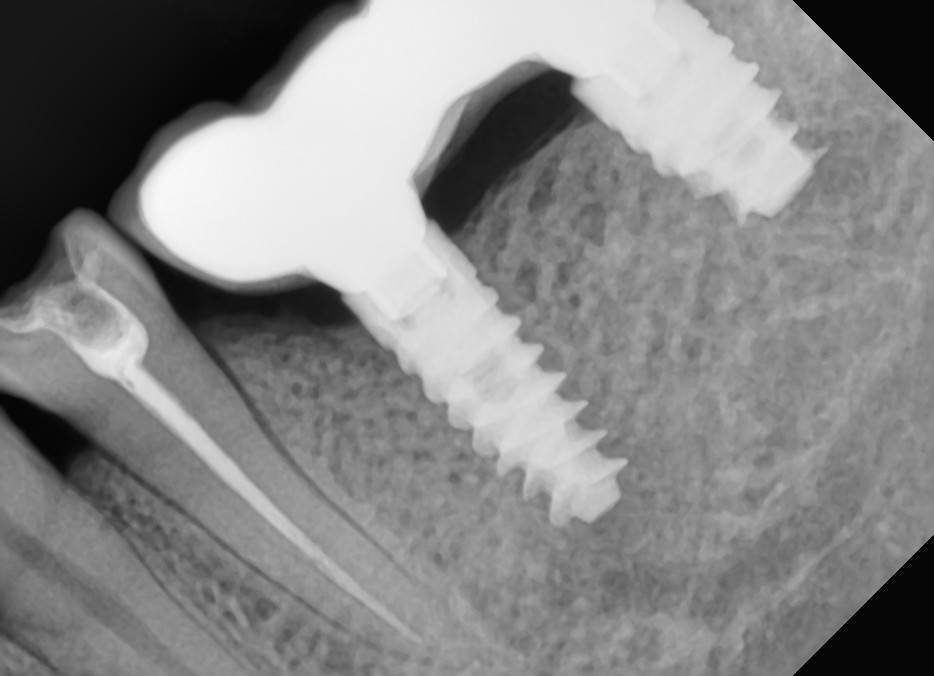

Aquarius Опубликовано 27 мая, 2022 Поделиться Опубликовано 27 мая, 2022 (изменено) 2016 г - установка имплантов. В то время находился под впечатлением от исследований Карлоса по гиперторку. Дал под сотню на дистальном импланте . Потом сильно пожалел))) Второй снимок - спустя 4 года на осмотре. https://wampi.ru/image/RZ3XaNg https://wampi.ru/image/RZ3XLcn Изменено 27 мая, 2022 пользователем Aquarius Ссылка на комментарий

Aquarius Опубликовано 28 мая, 2022 Поделиться Опубликовано 28 мая, 2022 (изменено) Ага, сам не понимаю почему. Аж в аппроксималку кость полезла . Несмотря на огрехи в протетике . И ни о каком остеоиде здесь речи быть не может. Вдобавок хирургия без каких-либо наворотов в виде ССТ и т.д. Трофика при нагрузке, единственное объяснение Изменено 28 мая, 2022 пользователем Aquarius Ссылка на комментарий